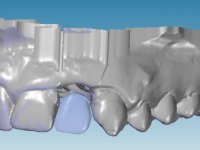

An impression was made on the implant with open tray technique using soft and regular consistency putty. At the laboratory, after confection of the work model, a diagnostic waxing was performed, which sought to find an aesthetic compromise solution. In this sense, a temporary workpiece screwed onto the implant was used to simulate the difficulties we would have with screwing the definitive work. This study abutment consisted of wax to reproduce soft and hard tissues, seeking to anticipate the use of ceramics of gingival and coronary shade. Also, part of the interproximal papillae corresponding to the distal portion of the 2.1 tooth and the mesial tooth of the tooth 2.3 were also waxed, anticipating the use of composite resin “chips” with gingival tonality. Finally, a veneer was waxed to correct the microdontia of the tooth 1.2. In this waxing, the vestibular emergence of the orifice for access to the screw of the implant abutment was evident. Once this therapeutic option was accepted, the implant abutment in polymerized composite resin was prepared at the lab, as well as the papillary "chips", also in composite resin of gingival tonality. Tested in the mouth, the abutment was screwed and the "chips" bonded. The access hole of the screw was filled with composite resin. In subsequent consultation, a gingivectomy was performed on the cervical contour of teeth 1.3, 1.2 and 1.1 with the aim of correcting the asymmetry between the first and second quadrant. After the soft tissues were cicatrized, a dental bleaching was performed according to the patient’s aesthetic requirements. Final impression on the implant was made using the silicone open tray technique, taking care to individualize the transfer piece by copying the emergence profile of the patient’s provisional abutment. At the laboratory, the impression yielded a definitive working model, on which the abutment was waxed on a plastic insert. This process was carried out with the orientation of a wall of silicone based on diagnostic waxing. The wax made on the plastic part was placed in a special holder that allowed its scanning in a laboratory scanner. This scan by CAD process informed the design of an abutment in Zr. later materialized by a CAM process. The Zr. abutment was tested in the mouth, validating its clinical and imaging establishment. During this consultation, the choice of color was made by the ceramist, of both the coronary ceramics and the ceramic of gingival tonality to be used. Individualized color scales were used. At the laboratory, the coronary and gingival ceramics were placed on the implant abutment and later, on a working model with refractory gypsum, a veneer of feldspathic ceramic was made. This veneer was built on a surface specially designed for this purpose in the abutment. This surface tried to reproduce a dental preparation performed for the same effect. In the mouth the abutment was screwed with a torque of 35N, the access hole to the screw was filled with Teflon and later filled with composite resin. The veneer was bonded onto the implant abutment using the conventional bonding technique, with relative insulation. For economic reasons, the patient did not proceed to perform the veneer on tooth 1.2. Although a limited aesthetic compromise was expected from the outset, a result was achieved which satisfied the patient.